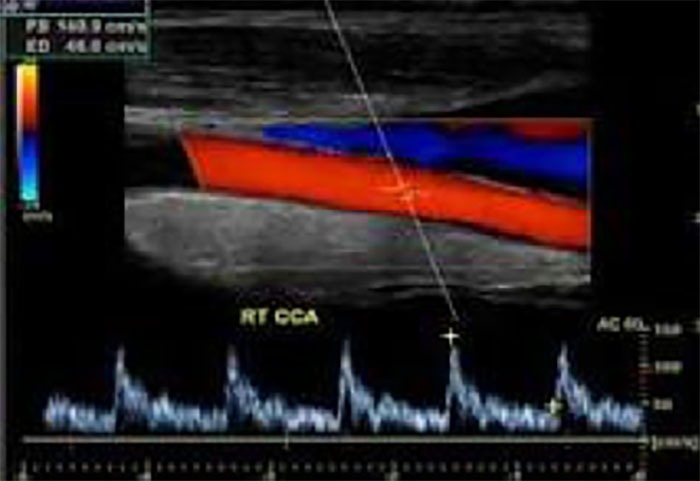

A Carotid ultrasound is done to detect plaque buildup in one or both of the carotid arteries in the neck and to see whether the buildup is narrowing your carotid arteries and blocking blood flow to the brain. Test results will help your doctor plan treatment.

You will lie on your back on an exam table for your test. The ultrasound sonographer will put gel on your neck where your carotid arteries are located. The gel helps the sound waves reach your arteries. The sonographer will move the transducer against different areas on your neck. The transducer will detect the sound waves after they have bounced off your artery walls and blood cells. The ultrasound system will use the sound waves to create and record pictures of the inside of your carotid arteries and to show how blood is flowing in your carotid arteries.